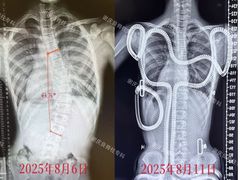

点小评9867739952 | 25-08-11